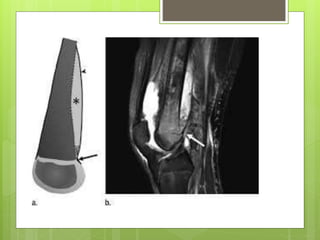

Pathophysiology of hematogenous seeding.When under pressure, exudate

Pattern of spread of infection. From the initial metaphyseal focus, the

Pathophysiology of hematogenousseeding.When under pressure, exudate or abscess can extend through Volkmann canals into subperiosteal region and from there into medullary cavity or epiphysis.

Pattern of spreadof infection. From the initial metaphyseal focus, the infection can spread into the epiphysis, the joint space, the subperiosteal space, the soft tissues, and the shaft of the bone.